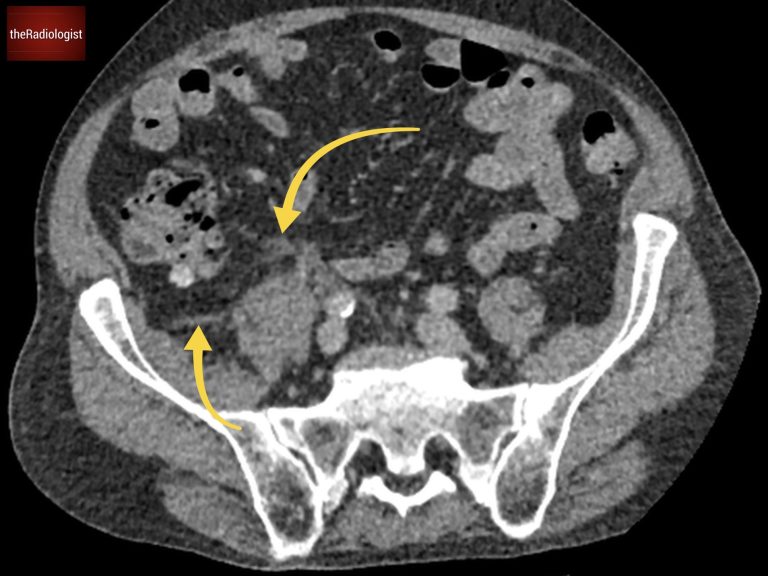

If we look at the psoas muscles which lie on either side of the vertebrae, we can see there is some asymmetry.  The right psoas is larger than the left and we’ve lost some of the fat planes within the muscle. This is subtle but make sure you compare the psoas muscles on every CT you look at. They look a bit like Mickey Mouse ears to me so you’re looking to see if the ears are symmetrical.

Compare the psoas muscles side by side. The right sided psoas muscle appears expanded with a loss of its normal fat planes.

Also as we scroll down we can see there is fat stranding surrounding the psoas muscle extending into the pelvis.

There is fat stranding surrounding the psoas extending into the pelvis.